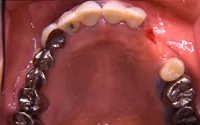

生まれつき歯が生えてこなかったケース

■治療前:生まれつき下顎左右前歯がなく隙間がある

■治療後:矯正治療後、下顎左右3番の2本にインプラント治療

| 主訴 | 生まれつき歯がなく隙間があり、審美障害・咀嚼機能障害がある |

| 治療方法 | インプラント治療 + 矯正治療 |

| 治療期間 | インプラント治療 約6ヶ月 |

| 通院回数等 | インプラント治療 約6回 |

| 費用 | 約94万円(税込) |

| リスク・副作用 | 術後の腫れ・痛み |